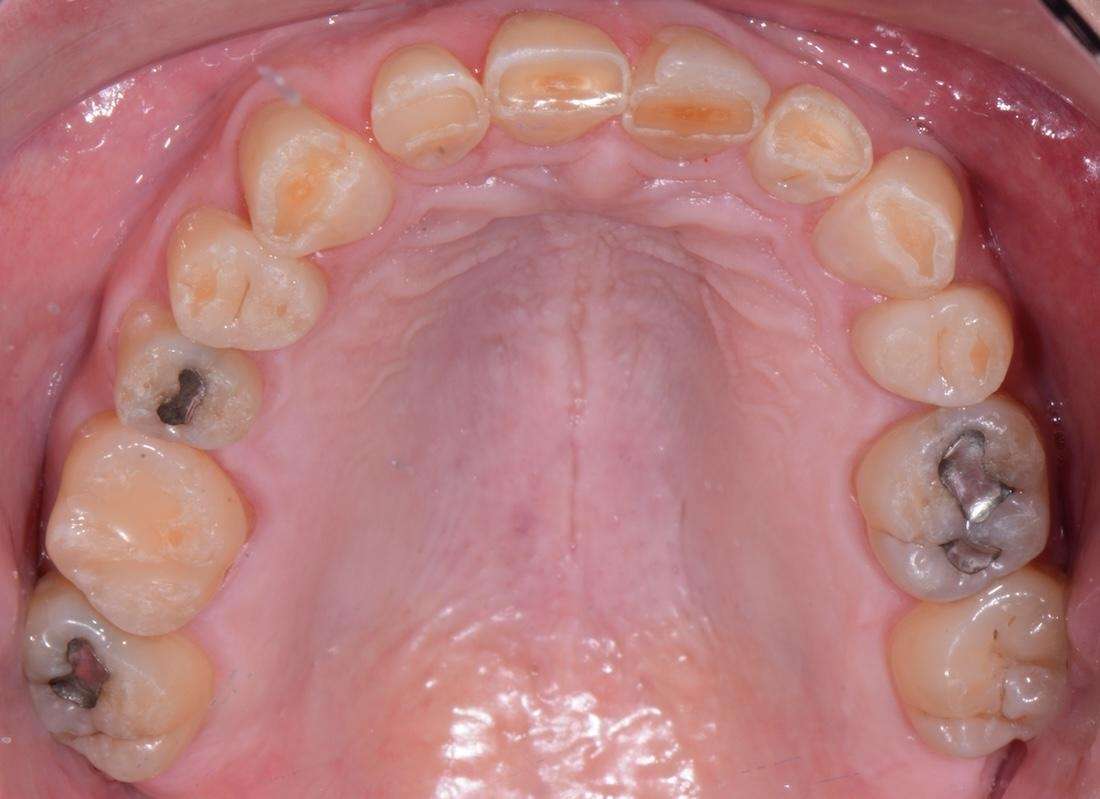

Upper and Lower Porcelain Crown Full Mouth Reconstruction (28 Teeth).

This patient came to us after years of frustration. Despite two rounds of orthodontic treatment as an adult, their teeth did not move as expected because some were fused to the jawbone. This led to a misaligned bite that caused severe wear on the front teeth. To make matters more challenging, acid reflux, nocturnal bruxism, and an uneven bite had further damaged their smile.

At first, I tried conservative bonding on the upper front teeth, but it simply could not hold up against the patient’s bite issues. After careful planning, I completed a full mouth reconstruction with porcelain crowns. This allowed me to open and correct the bite, restore proper function, and dramatically improve the aesthetics. The final result was a balanced, healthy, and natural-looking smile that gave this patient their confidence back. I especially enjoyed this case because it demonstrates that complex, full mouth reconstructions are not limited to prosthodontists. With advanced training, a general dentist like myself can achieve outstanding results for even the most challenging cases.